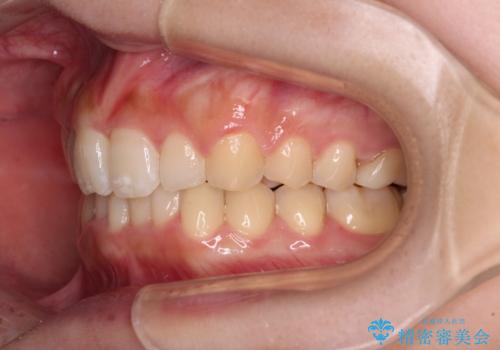

- 上顎の重なっている前歯を気にして来院された患者様です。

八重歯改善には抜歯が必要で、八重歯の移動量が多く、更には右側にずれている正中を改善する必要がありました。

インビザライン単体での治療は困難と判断し、補助装置により八重歯移動後にインビザラインを用いることとしました。

インビザラインでは治療期間が延びることが予想されたため、ワイヤー矯正を提案しましたが、セラミッククラウンが多く、壊すあるいは傷が付く可能性があることから、長期間であってもインビザラインを選択されました。